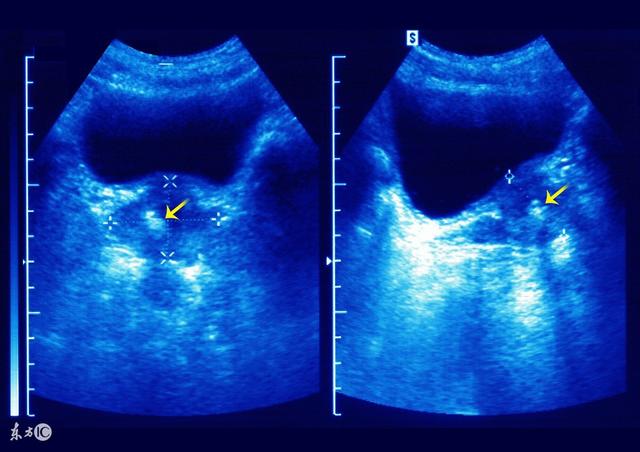

冲击波排出前列腺钙化灶 显微镜可见前列腺结石排出